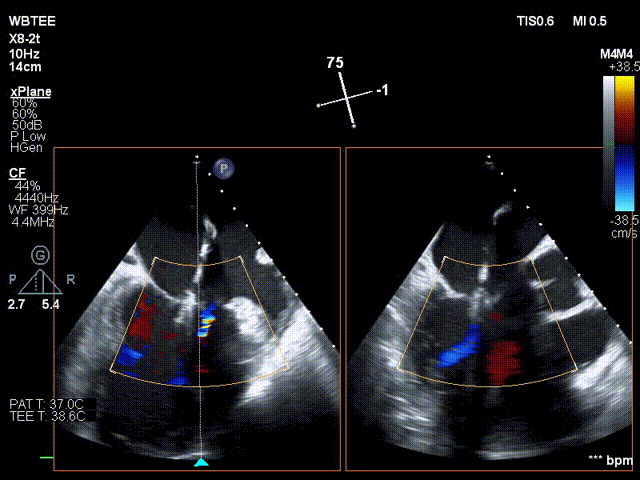

术前行经食道超声评估

原发性二尖瓣反流,反流程度4+;二尖瓣瓣口面积4.15cm²,平均跨瓣压差5mmHg,二尖瓣前叶(A2)长度23.35mm,二尖瓣后叶长度(P2)长度13.2mm;左室射血分数67%。患者手术风险高,操作难度大,经心脏瓣膜团队多次充分讨论评估后,决定行经导管二尖瓣缘对缘修复治疗。

术前MDT策略:从解剖结构来看二尖瓣后叶脱垂伴连枷涉及整个2区,累及3区和1区,宽度15mm左右,且连枷高度甩起高度有7-8mm,可见长达10.4mm的飘样回声,术前策略预计使用两个二尖瓣夹,较小的二尖瓣口面积和较高平均跨瓣压差,是一次高难度的挑战。